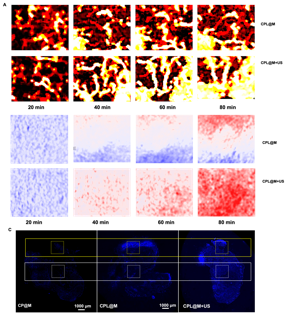

图3 (A) 肿瘤部位血液灌注情况;(B) 肿瘤部位氧气变化情况;(C) 肿瘤部位药物积累